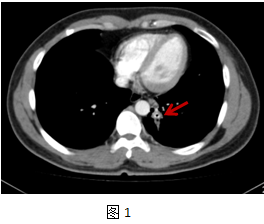

患者刘**,男,34岁,以“咳嗽咳痰2年余”为主诉入院。该患者近2年反复刺激性咳嗽,少量白粘痰,在当地医院反复抗感染治疗无效。入院前胸部CT片显示:左肺下叶后基底段结节性质待定。肺病科徐顺贵副主任医师和胸外科陈阳天主任医师仔细阅读患者外院胸部CT片后发现左肺后基底段支气管处有一圆柱型高密度影,考虑支气管异物可能(图1,2),详细追问病史,患者9岁时嬉闹时误吸一玩具子弹,当时咳嗽较剧,后症状缓解。近2年患者间断有咳嗽、咳痰,症状逐渐加重。